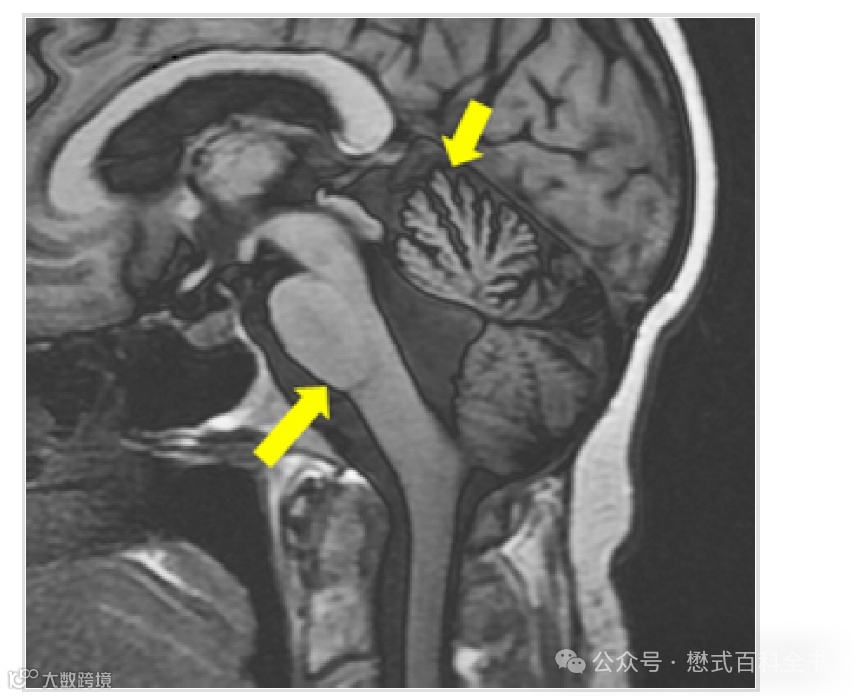

图13:IR序列实图重建

采用实图重建之后,就没有所谓的反弹现象了。即使在零点(null point),信号也不是黑色的,而是灰色的,因为磁化矢量如果在负方向,其信号强度才是最低的。

图14:IR序列实图重建图像

IR序列实图重建一个显著的特点就是,背景是灰色的,因为此时信号强度为0反而不是最低值,还有负值(类似大家可以这样理解)。而且实图重建的对比度更好。

采用实图重建的话,不仅接收信号的大小,还接收相位。在磁敏感变化大的区域或者主磁场不是太均匀的区域,则相位差异可能由于均匀性的因素,不一定是180°,造成相位错误的累积,形成伪影。

图15:IR序列实图

如图15,IR序列采用实图重建,背景是灰色的。虽然不会产生反弹点伪影,但是注意看颈部,还是有些相位错误导致的小伪影。